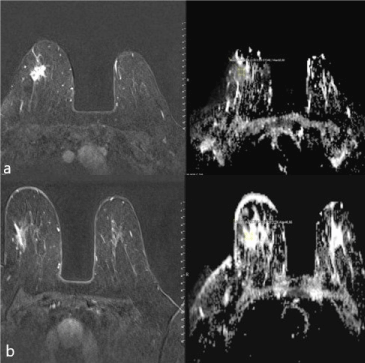

Size of the tumor obtained after surgery, histopathological type and Ki-67 index value are presented in Table 1b (Figure 2a-b). The median Ki-67 index of the patients was calculated as 20 (min: 6-max: 80). The median tumor size obtained after surgery was 1 (min: 0-max: 4) cm. Invasive ductal carcinoma was present in 92.3% (n = 36) of the lesions in the pathological subtyping, whereas invasive lobular carcinoma was present in 7.7% (n = 3).

Figure 2a-b. ADC mapping and T1 weighted subtraction imaging of a 45-year old case with LABC detected to have invasive ductal carcinoma at right breast. a) A 57x45x38 mm mass lesion with a spiculated contour on MRI and a mean ADC value of 0.75 before NAC b) After NAC, mass dimension was reduced to 25x20x20 mm and the mean ADC value increased to 1.5. Surgically removed tumor size and size measured on MRI after NAC were similar and 25x18x20 mm.